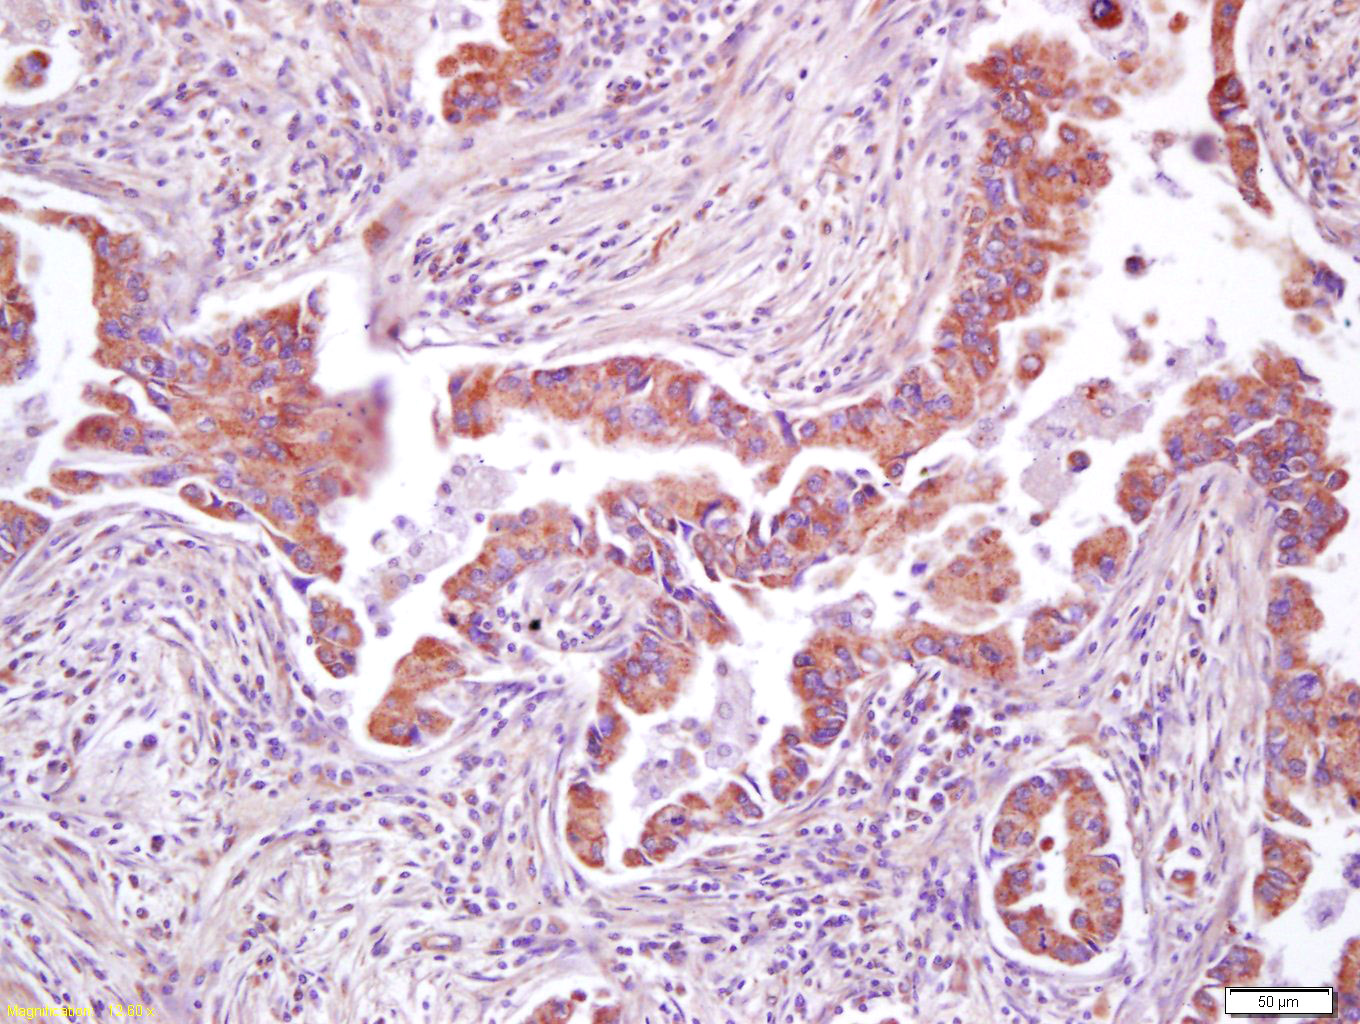

Tissue/cell: human kidney tissue; 4% Paraformaldehyde-fixed and paraffin-embedded; Antigen retrieval: citrate buffer ( 0.01M, pH 6.0 ), Boiling bathing for 15min; Block endogenous peroxidase by 3% Hydrogen peroxide for 30min; Blocking buffer (normal goat serum,C-0005) at 37℃ for 20 min; Incubation: Anti-AMPK beta 2 Polyclonal Antibody, Unconjugated(bs-3967R) 1:200, overnight at 4°C, followed by conjugation to the secondary antibody(SP-0023) and DAB(C-0010) staining

Tissue/cell: human lung carcinoma; 4% Paraformaldehyde-fixed and paraffin-embedded; Antigen retrieval: citrate buffer ( 0.01M, pH 6.0 ), Boiling bathing for 15min; Block endogenous peroxidase by 3% Hydrogen peroxide for 30min; Blocking buffer (normal goat serum,C-0005) at 37℃ for 20 min; Incubation: Anti-AMPK beta 2 Polyclonal Antibody, Unconjugated(bs-3967R) 1:200, overnight at 4°C, followed by conjugation to the secondary antibody(SP-0023) and DAB(C-0010) staining